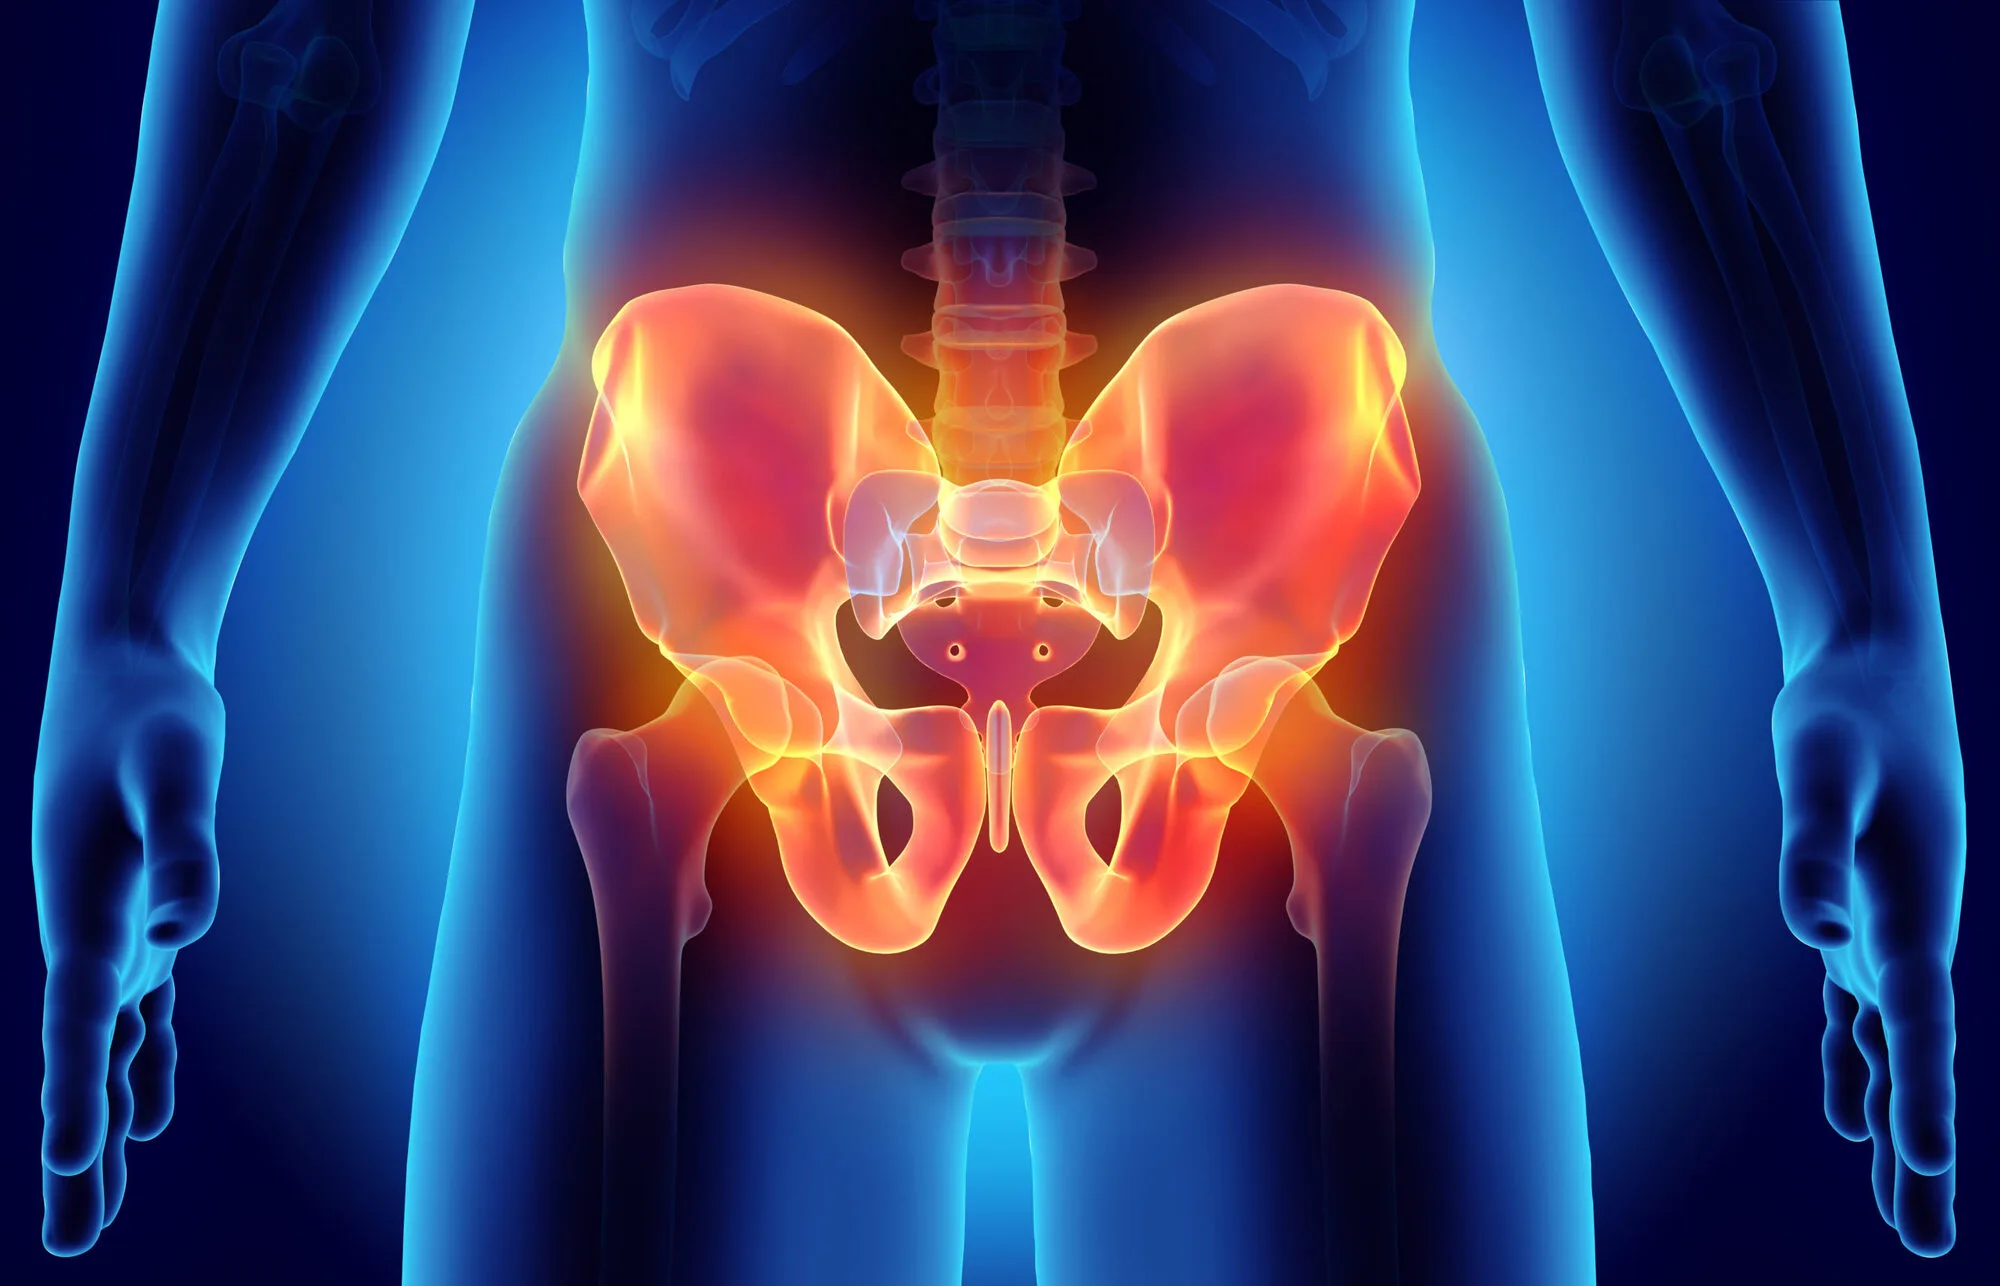

La fractura de pelvis es una lesión grave que afecta uno de los huesos más importantes del cuerpo, ya que sostiene el peso corporal y protege órganos vitales.

Ocurre cuando uno o más huesos de la pelvis se rompen debido a un trauma o impacto fuerte.

- Dolor intenso en la cadera o zona pélvica